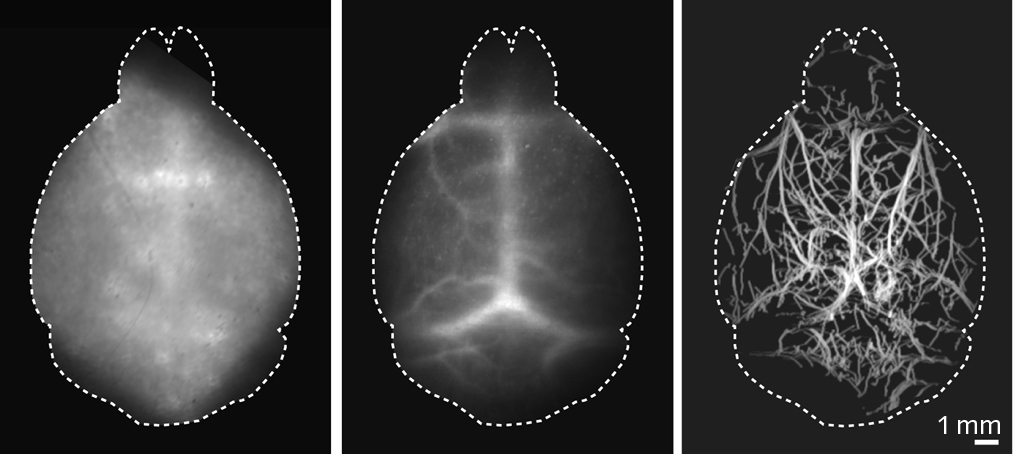

Specifically, the Zurich team’s DOLI technique takes advantage of the NIR-II spectral window spanning from 1000 to 1700 nm. This exhibits less scattering and can effectively reduce background autofluorescence signals (see figure). “By localizing a sparsely labeled contrast agent within the NIR-II window,” Razansky says, “DOLI enables superresolution imaging through a diffuse medium, such as the murine brain, noninvasively.”

The group’s goal in their recent research has been to image even deeper into the brain, for an even better and more comprehensive study of it. Visualizing biological processes deep in the intact living brain is crucial for understanding both its cognitive functions and neurodegenerative diseases such as Alzheimer’s and Parkinson’s. The researchers say that with their new DOLI method, they have been able to clearly visualize the microvasculature and blood circulation deep in the mouse brain entirely noninvasively for the first time. This ultimately enables a closer look at a living, functioning brain.